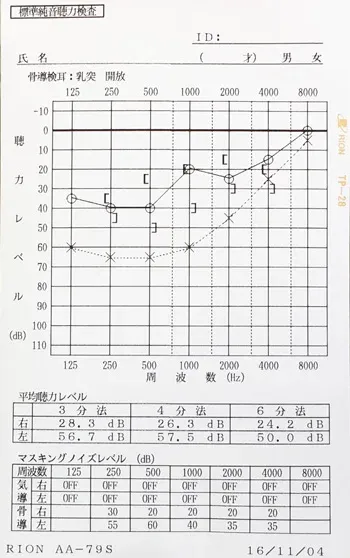

突発性難聴の治療で高圧酸素室に入って治療をした時、耳ぬきがうまくいかずに滲出性中耳炎になってしまいました。痛みは無いので鼓膜に穴をあけるのもとても不安です。滲出性中耳炎は、鍼治療でよくなりますか?